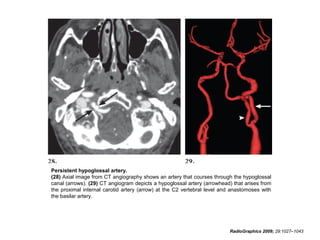

Primitive Hypoglossal Artery

• The persistent hypoglossal artery is the second

most common carotidvertebrobasilar artery

anastomosis, with a prevalence of 0.02%–

0.10%.

• The persistent hypoglossal artery originates from

the internal carotid artery at the levels of the C1

through C3 vertebral bodies, courses through

the hypoglossal canal, and anastomoses with

the basilar artery.

• A primitive hypoglossal artery does not

passthrough the foramen magnum.

RadioGraphics 2009; 29:1027–1043

• In 79% of cases, the posterior communicating

arteries are hypoplastic, and in 78% of cases,

the vertebral arteries are hypoplastic.

• Definitive diagnosis is based on the recognition

of na anomalous artery in the enlarged

hypoglossal canal.

• A persistent hypoglossal artery has been

reported to cause glossopharyngeal neuralgia

and hypoglossal nerve paralysis.

Persistent hypoglossal artery.

(28) Axial image from CT angiography shows an artery that courses through the hypoglossal

canal (arrows). (29) CT angiogram depicts a hypoglossal artery (arrowhead) that arises from

the proximal internal carotid artery (arrow) at the C2 vertebral level and anastomoses with